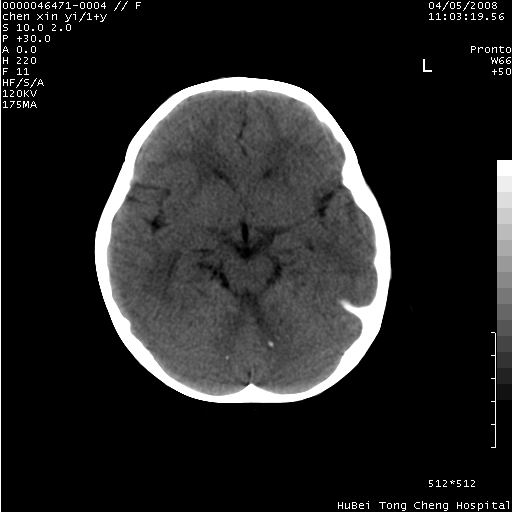

以下是引用zhangzhongshou在2008-4-9 12:54:00的发言:[br]请结合病史,有以下可能1、炎性肉芽肿钙化(含结核)2、寄生虫钙化(含脑囊虫)3、其他良性钙化性病变